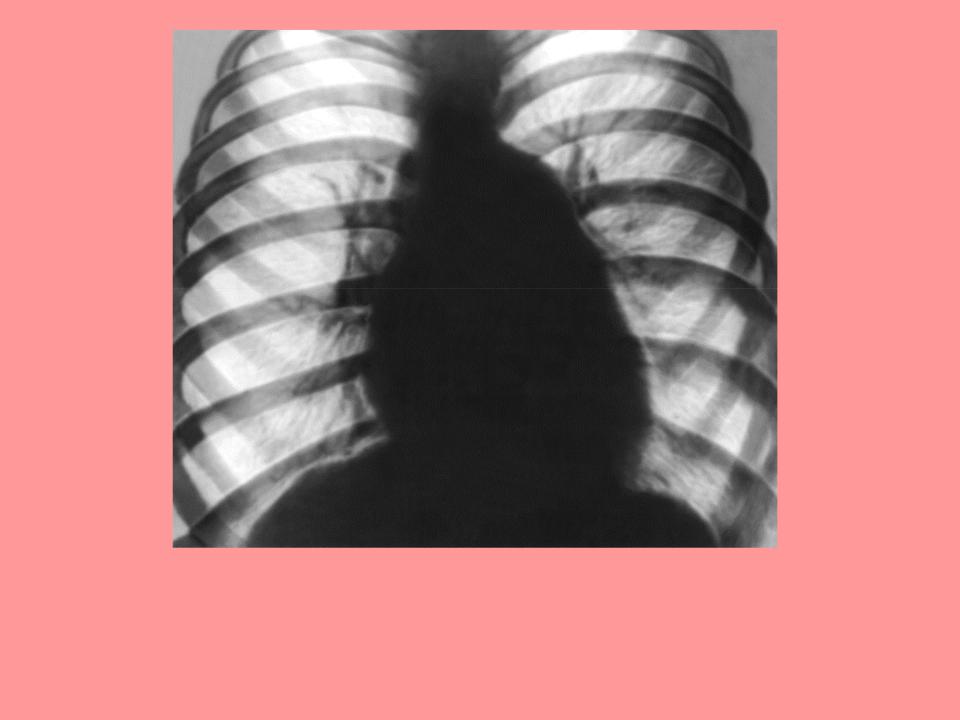

Рентгенограмма грудной клетки больного с митральным стенозом (передняя проекция):

признаки артериолярной легочной гипертензии: резко выбухает дуга легочного ствола, корни легких расширены, но структурны, расширенные тени артериальных ветвей как бы обрываются (симптом «ампутации»), по перефии лгких сосудистый рисунок «обеднен»; поперечник сердцаувеличен, митральнаякогнфигурация сердца.